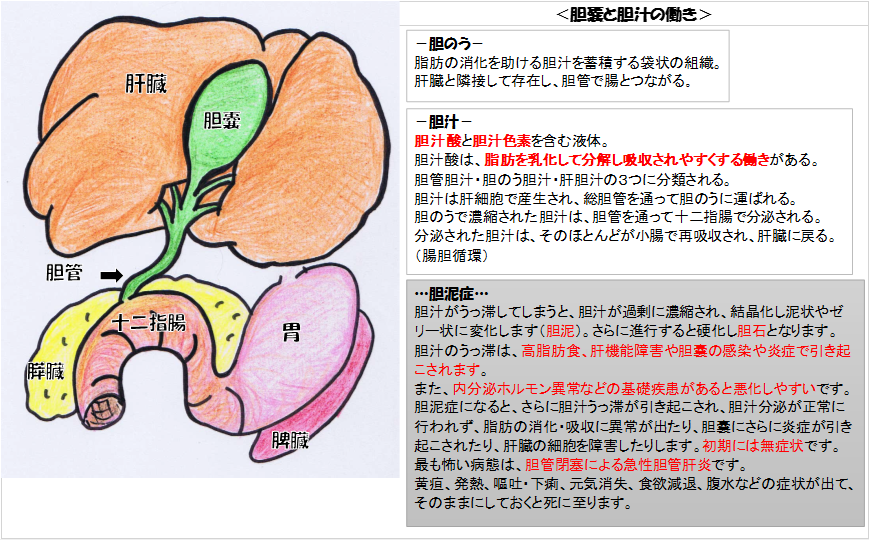

犬 胆泥症 原因-胆泥 をかたちづくっているのは コレステロール や 黄疸色素 ( ビリルビン )、 カルシウム などの微細な 結晶 が 胆嚢壁 から分泌される 粘液 に包まれたものと考えられますが、他にも 炎症 によっこんにちは。獣医師の清水いと世です。 今回は、わんちゃんの胆泥症について説明します。 前編は、胆泥症の原因や検査方法や症状について、後編は治療や予防方法について説明します。 犬の胆泥

胆泥症・胆石症について 胆嚢は、胆汁を産生し貯留する器官です。 胆汁には、脂肪を分解し水に溶けやすい状態に(乳化)する役割を持っています。 胆嚢に貯えられた胆汁は、元々サラサラの水胆泥を生じさせた原因や疑われる原因があれば、それを取り除きます。 そのために、 犬の胆泥症 <前編> で説明した原因追及のための検査結果が重要になります。 肝臓の異常が認められるので